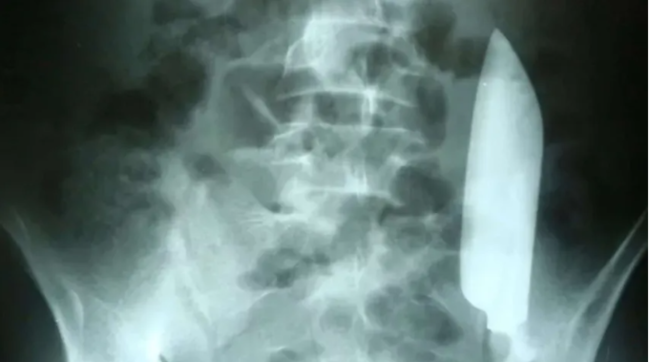

Xəbər verdiyimiz kimi, "Tesla" və "SpaceX" şirkətlərinin qurucusu, milyarder İlon Maskın "Neuralink" şirkəti ilin əvvəlində ilk dəfə insan beyninə çip yerləşdirib. Axşam.az xəbər verir ki, milyarder sahibi olduğu "X" sosial şəbəkəsində həmin şəxsin səhhətində